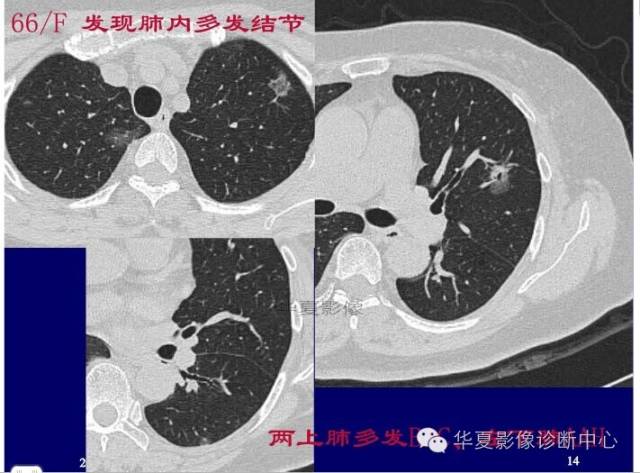

这一例是否GGO成分几乎没有

基本是实性的

那就按实性的分析

胸膜凹陷,分叶征